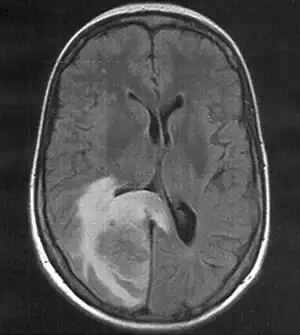

MRI (T2 flair) showing a brain metastasis with surrouding edema